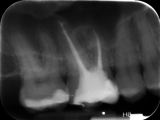

„Videoübertragung der ersten Live-Demonstration einer endodontischen Revisionstherapie an der Akademie: Entfernung der alten Wurzelfüllmaterialien“

„Videoübertragung der Behandlungssitzung mit Abschluss der Therapie: Die laterale kalte Verdichtungstechnik zur Wurzelfüllung“

Damals zwar bereits ein etabliertes Verfahren, jedoch mit einigen technischen Schwierigkeiten behaftet. So wurden während der Demonstration mehrere Methoden der Entfernung von Guttapercha aus den Wurzelkanälen gezeigt, die von der Handinstrumentation über die 360°-rotierende maschinelle Präparation bis hin zum thermoplastischen Erweichen von Guttapercha reichten. In der zweiten Live-Demonstration wurde dann beim gleichen Behandlungsfall vier Wochen später die laterale kalte Verdichtung von Guttapercha als Wurzelfülltechnik demonstriert. In der Bildergalerie zum Beitrag finden sich die dazugehörigen Röntgenaufnahmen.